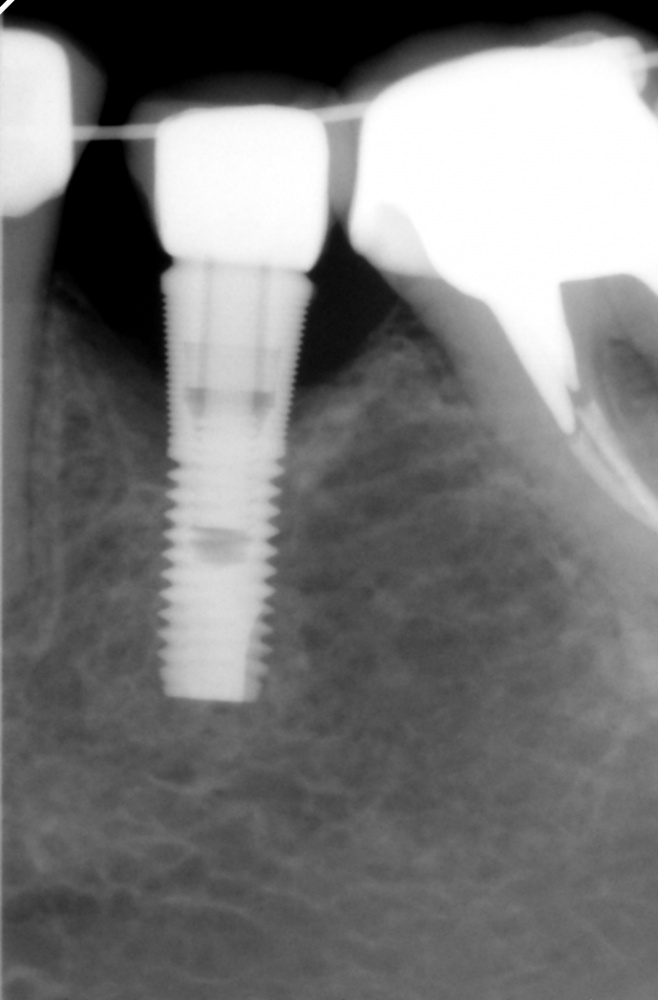

Между тем, в практике существует масса примеров, когда это правило не соблюдается, и расстояние от имплантата до соседнего зуба, либо от импланта до импланта существенно меньше назначенного Гамбореном Зукелливичем Урбаняном:

Не суть. Важно понять, что крутящий момент при установке имплантата — это решающий фактор, от которого, в дальнейшем будет зависеть как риск осложнений, так и состояние костной ткани вокруг имплантата. Или вокруг нескольких имплантатов:

Получается так, что между двумя имплантами остаётся сильно сжатый участок кости. Который, в случае I или II биотипа и так кровоснабжается не очень, а тут еще и сдавливается вхлам. Его кровоснабжение на нуле, а мы-то с вами знаем, что всё, что не кровоснабжается в нашем организме, отваливается нафиг. Нет питания — нет регенерации. К сожалению:

Чем меньше этот участок по размерам, тем больше он сдавливается, тем хуже его кровоснабжение.

Если по имплантологическому правилу #2 возникает необходимость установить имплантаты очень уж близко, достаточно сделать перепреп и добиться максимального снижения торка при установке — буквально, до 5 Нсм. Имплантат должен просто падать в лунку с ускорением G, не встречая никакого сопротивления. И всё на этом: